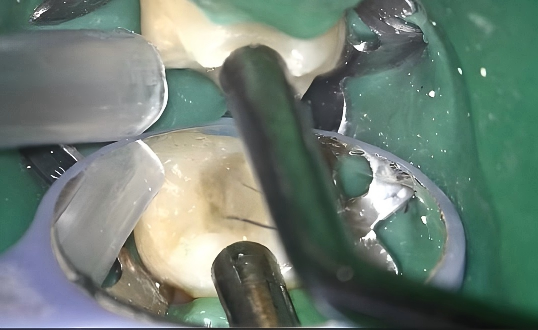

1. Isolation and Access Refinement

Rubber dam isolation was applied for moisture control. The access cavity was cleaned to remove residual debris and expose sound dentin surfaces for adhesive procedures.

2. Etching

P-Etchant phosphoric acid etchant was applied to enamel and dentin. The surface was thoroughly rinsed and dried to prepare it for bonding.

3. Adhesive Application

HugeBond light-cure dental adhesive was applied to the cavity walls, evenly dispersed with gentle air, and then light-cured to achieve reliable bonding.